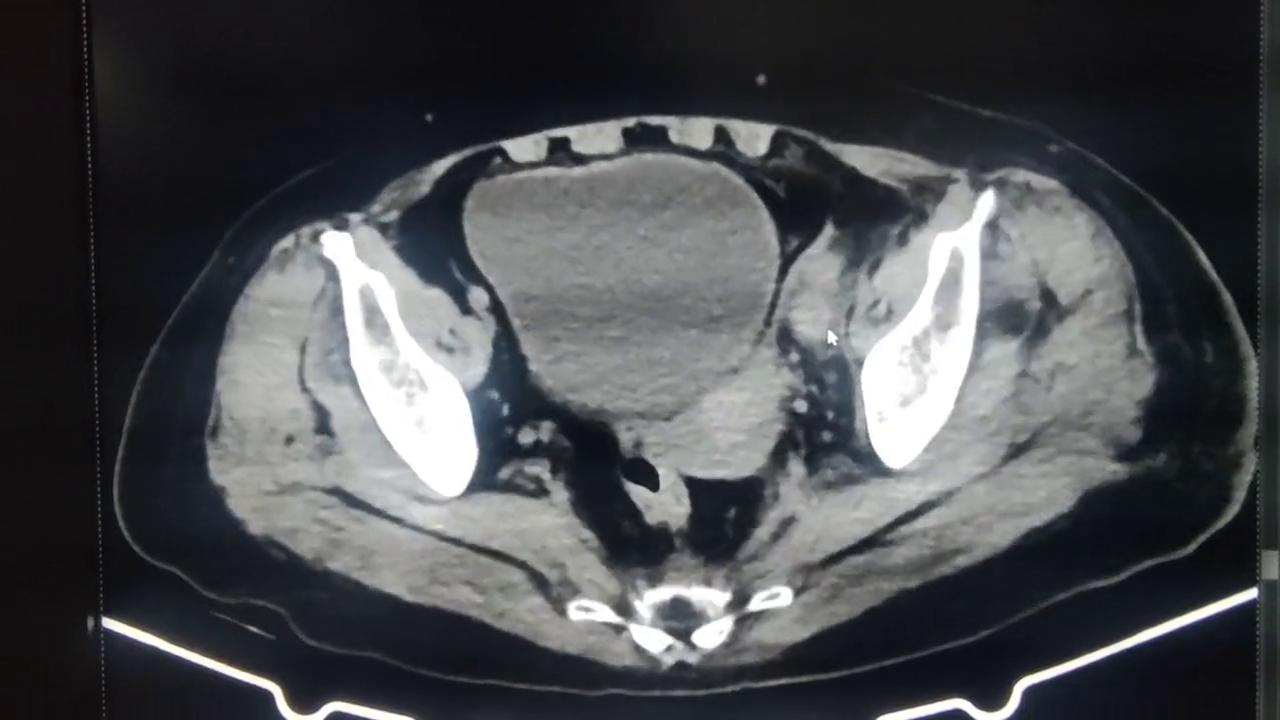

哈喽各位老铁!今天看一个下肢深静脉血栓的病人,他后来是经过介入治疗之后的。这个人是左髋关节置换术后的,由于卧床还有可能血液高凝导致的下肢深静脉血栓。当时做了一个CT,带到了一部分髂静脉,可以看到左侧髂总静脉还有髂外整个腔内密度是高的,而且血管比较粗,周围的脂肪间隙比较模糊。

这个给他做完介入之后,给他放支架,因为这个地方的血栓比较多,而且抽不出来,所以放支架给他盖住。治疗之后管腔里高密度的,高密度是没有了,就是高密度血栓,血栓基本没有了,血管周围的渗出也基本看不到了。